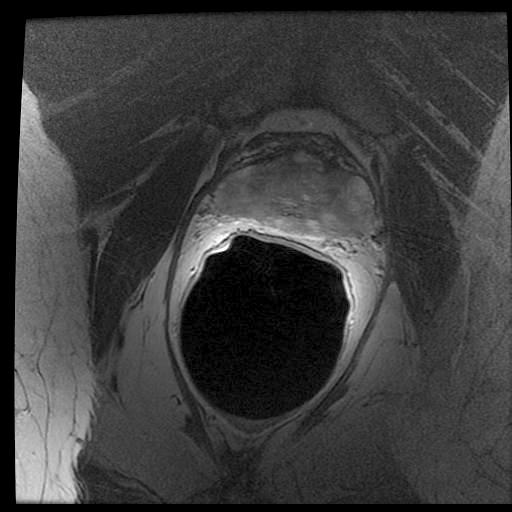

In the previous section, we simulated images in order to exploit “perfect segments”. In this section, we validate our approach using actual MR images of prostates. The image data from 15 patients were manually delineated by 5 oncologists.

The MR images used in this study were derived from an online database444http://prostatemrimagedatabase.com/. The database contains T2-weighted MR volume datasets, provided by Brigham and Women’s Hospital, the National Center for Image-guided Therapy, and Harvard Medical School. The images comprised T2-weighted MR images (T2W-MR) with endorectal coils. The pulse-sequence groups in the DICOM headers of most of the T2-weighted images were marked fast-spin echo (FSE), although some were marked as fast-relaxation fast-spin echo-accelerated (FRFSE-XL). The dataset contained images with slice thickness ranging from 2.5mm to 4.0mm, and varying contrast levels and signal-to-noise characteristics. All of the images were captured at a depth of 16 bits, and they varied in size from 256256 to 512512 pixels.

Sample images are depicted in Figure 6 (top row). Generally, one assumes that prostate segmentation is a relatively easy task. However, the variability of such segmentation remains considerable, and this is conspicuous in Figure 6 (bottom row).